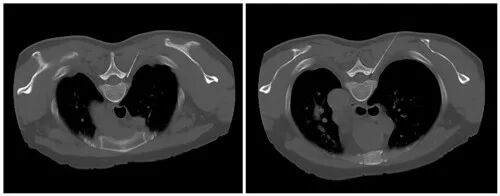

10月10日下午,在放射科全力配合下,王鑫主治醫(yī)師和梁慧靈管床醫(yī)生為患者完成了CT引導(dǎo)下右側(cè)胸3、胸4神經(jīng)根脈沖射頻術(shù)。

胸3、胸4神經(jīng)根脈沖射頻術(shù),治療神經(jīng)痛

神經(jīng)根脈沖射頻術(shù)術(shù)中

術(shù)中能精準(zhǔn)復(fù)制疼痛區(qū)域,術(shù)后當(dāng)天疼痛明顯緩解,48小時(shí)后觀察,患者疼痛緩解出院。該手術(shù)鎮(zhèn)痛效果好、創(chuàng)傷小、費(fèi)用低,安全性高,并發(fā)癥少,能有效提高患者的生活質(zhì)量。“疼痛,無須再忍!”